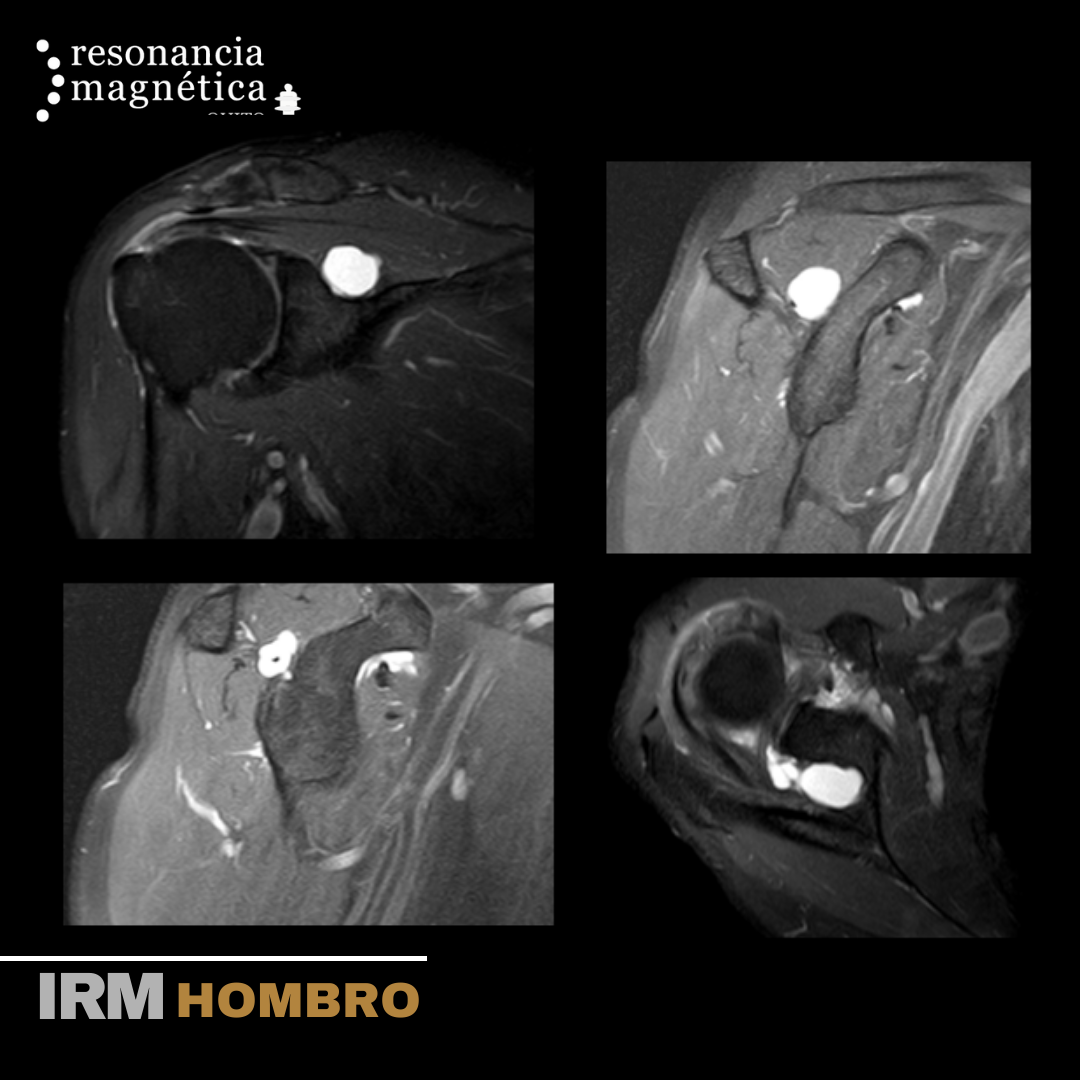

RM Hombro

La RMN del hombro provee imágenes detalladas de las estructuras dentro de la articulación del hombro, incluyendo huesos, tendones, músculos y vasos, desde cualquier ángulo. La resonancia magnética nuclear (RMN) es un examen no invasivo que los médicos utilizan para diagnosticar enfermedades.